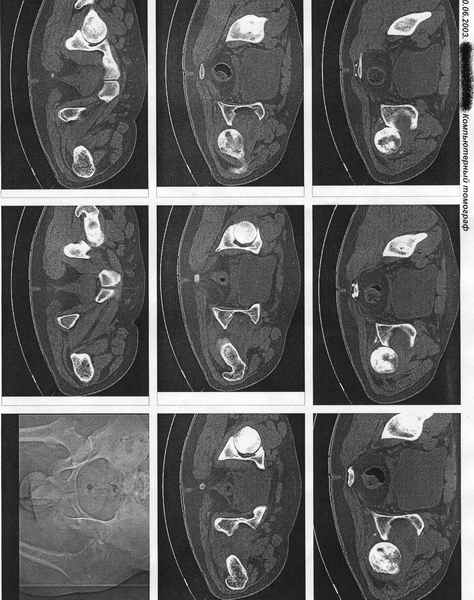

Ко мне поступил из района пациент с 7-ми месячным вывихом бедра. Возраст 25 лет. Прилагаю КТ по которой виден АНГБК. Интересно услышать ваши мнения по тактике лечения. Из эндопротезов доступен ЭСИ. С Уважением Андрей Стасюк